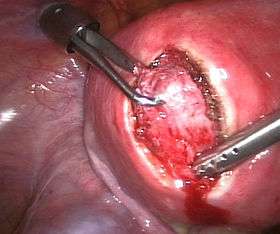

![]() | |

| Uterine fibroids as seen during laproscopic surgery | |